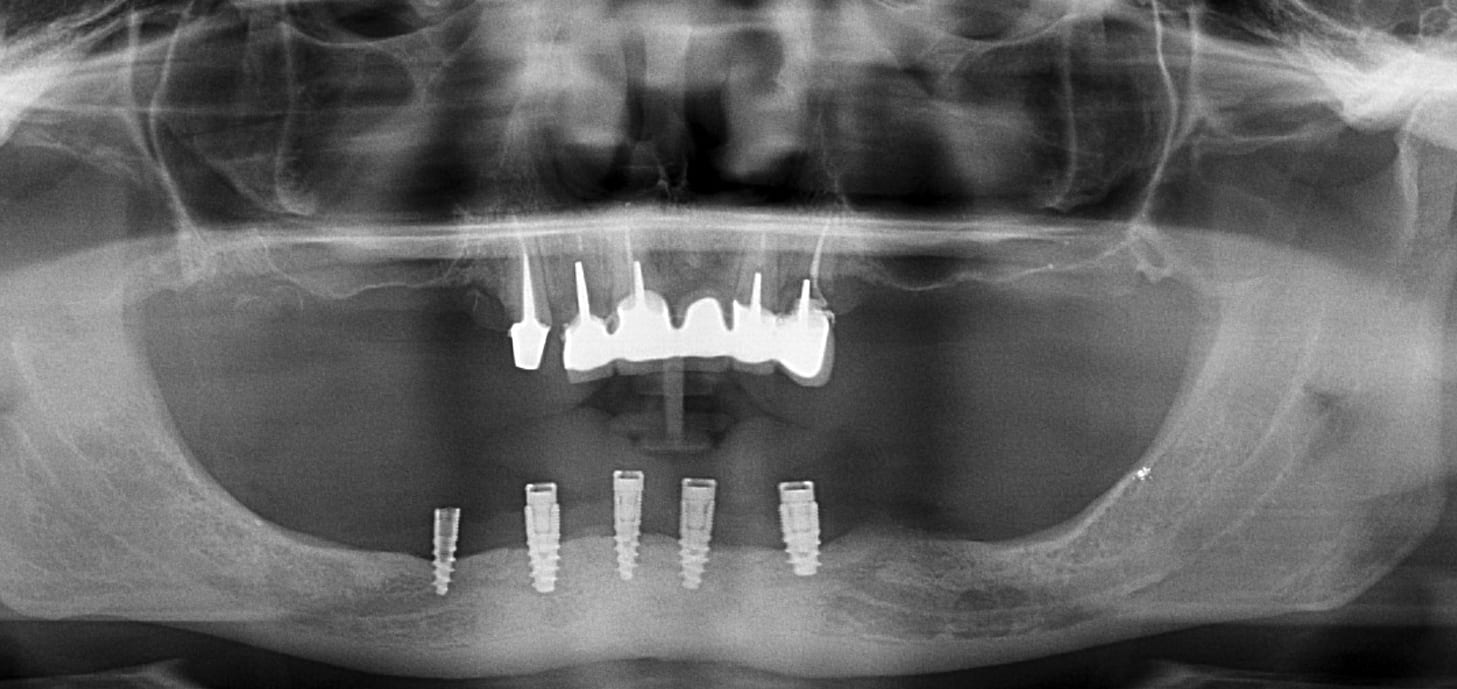

Patient 2 :

2 implants isolés de chez le même dentiste (Liban :-), décédé hélas également. )

Radio 2, rien d’identifiable sérieusement avec une pano

Bonjour je te remercie pluton, je vais essayer une rétro-alvéolaire pour le deuxième patient. Lors de son prochain rendez-vous